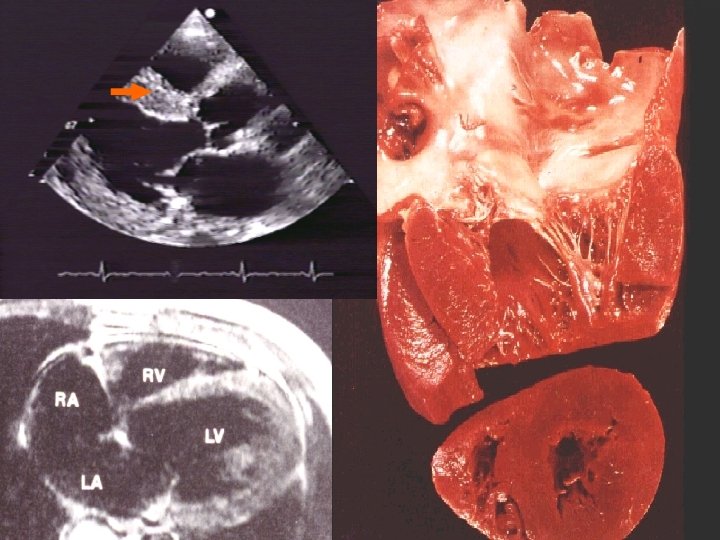

DISFUNCION SISTOLICA: • Disminución de la función de bomba, con disminución de la fracción de expulsión (< 50%). • Etiología: Cardiomiopatía dilatada, Cardiopatía Isquémica, Hipertensión, Valvulopatías.

DISFUNCION DIASTOLICA: • Trastorno en la relajación con llenado anormal que produce congestión pulmonar y disminución del volumen sistólico. • Etiología: Hipertensión, Cardiopatía Isquémica, Cardiomiopatía Hipertrófica, Cardiomiopatía Restrictiva